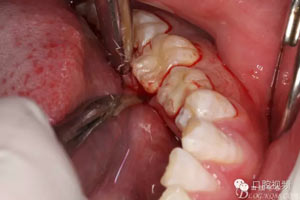

圖5.行齦溝內(nèi)水平切口,不建議做垂直附加切口,因為口底組織淺,容易水腫。風(fēng)險大。

圖6.翻瓣、形成袋形瓣